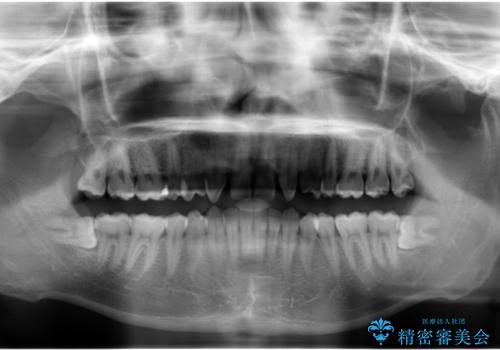

生まれつき上の歯が二本少ない状態でした。

バラバラに位置している前歯の位置を矯正治療で修正してからブリッジを装着しています。

また、全体矯正もご希望でしたので下の歯のがたつきや、すれ違っているかみ合わせも治療しています。

親知らずは矯正前に抜歯しています。